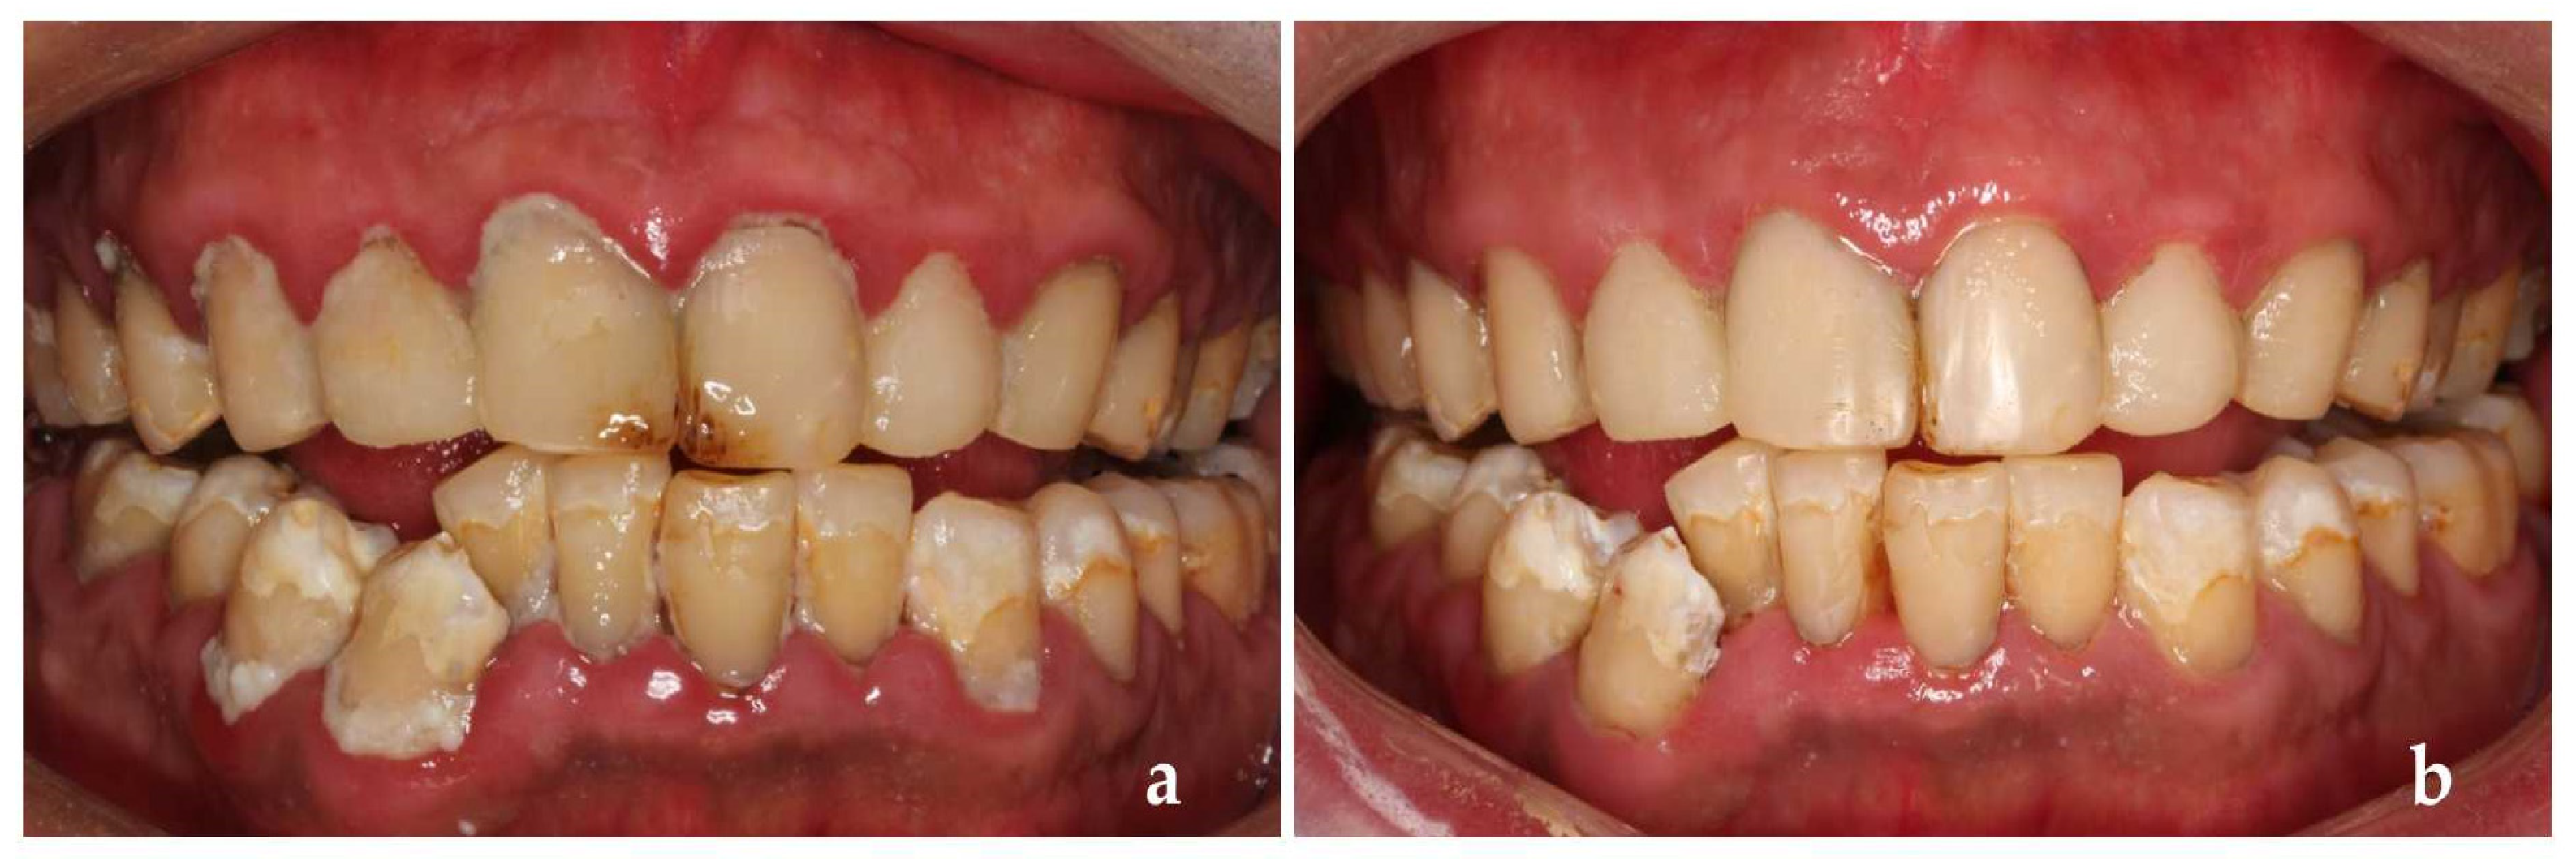

Figure 4.

(a–c) During the first treatment; (d–f) First treatment completed.

The patients’ general information was recorded into the Dental Caries Management Software. First, the history of present disease, systemic history and dental examination were recorded into the software. Secondly, a caries risk questionnaire was completed by the patient who had a visible caries decay, adjacent caries, white spot lesions on the smooth surface of teeth and restorations filled within 3 years. The detection of Streptococcus mutans (MS) and Lactobacillus (LB) in his mouth was either moderate or severe, and most of his teeth surface was covered with visible dental plaque. He liked to drink Coca-Cola and eat snacks frequently, which might be the main etiology of his caries. After the above information was input into the software, the caries risk rating assessed by the software was high level, and relevant suggestions on caries management were given to patients (Figure 3a,b). Then, we evaluated the difficulty of treatment. There were class I–V cavities in his teeth, almost all teeth were severely damaged by decay. Some teeth had a history of restoration or filling failure. The patient had no pharyngeal reflex or dental phobia but had excessive salivation. Taking all these into consideration, we planned to use composite resin restoration/glass ionomer transition repair for posterior teeth and minimally invasive techniques for anterior teeth. After the above information was put into the software, we came to the conclusion that the patient’s treatment difficulty rating was Grade III and recommended referral to a grade C dentist (dental aesthetic specialist and caries clinical specialist) for treatment (Figure 3c). With the cooperation of the dentists, the patient’s initial treatment was satisfactory (Figure 4a–f).